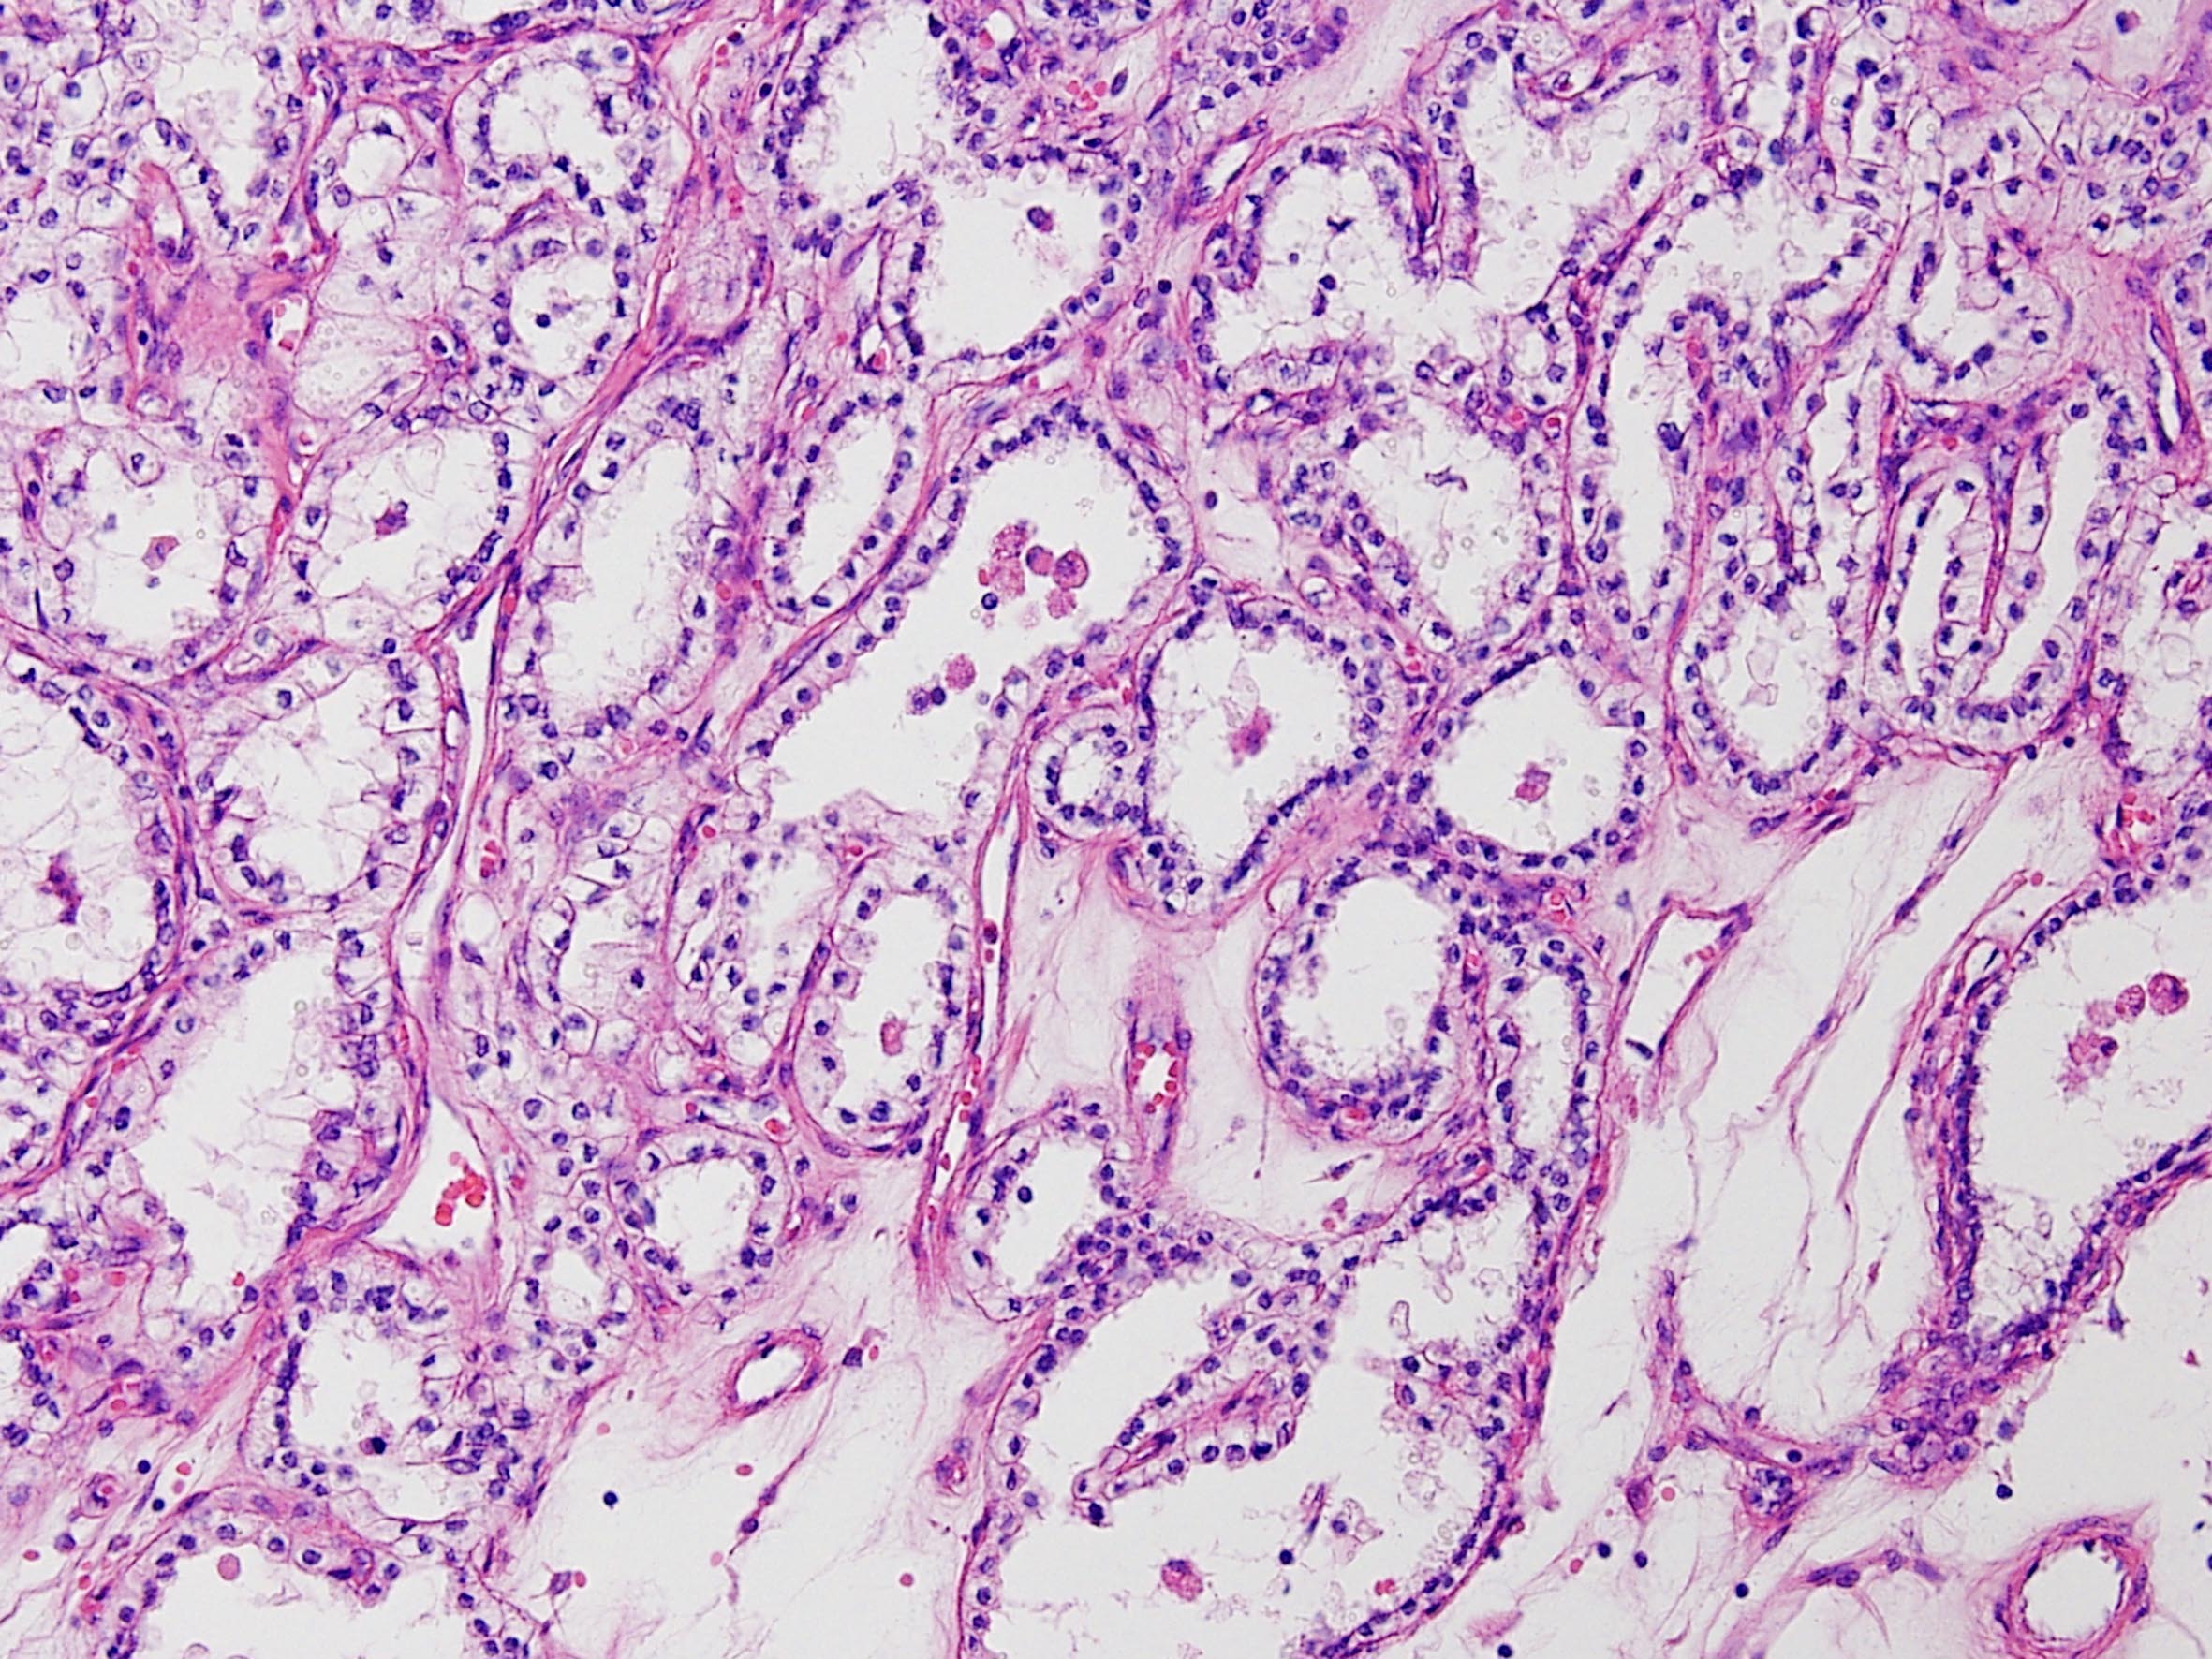

Classification of renal tumors

Case ID: 164